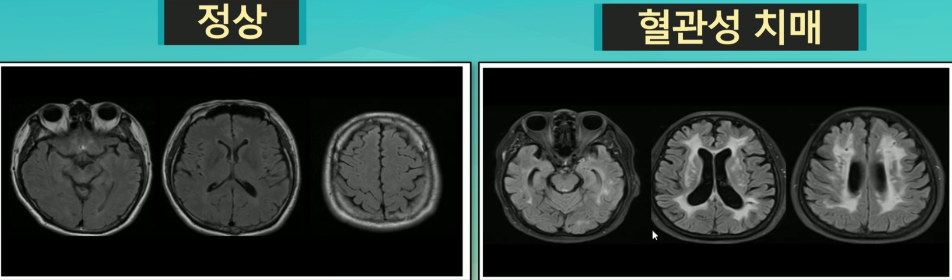

세가지 치매

알츠하이머치매,혈관성치매,알콜성치매